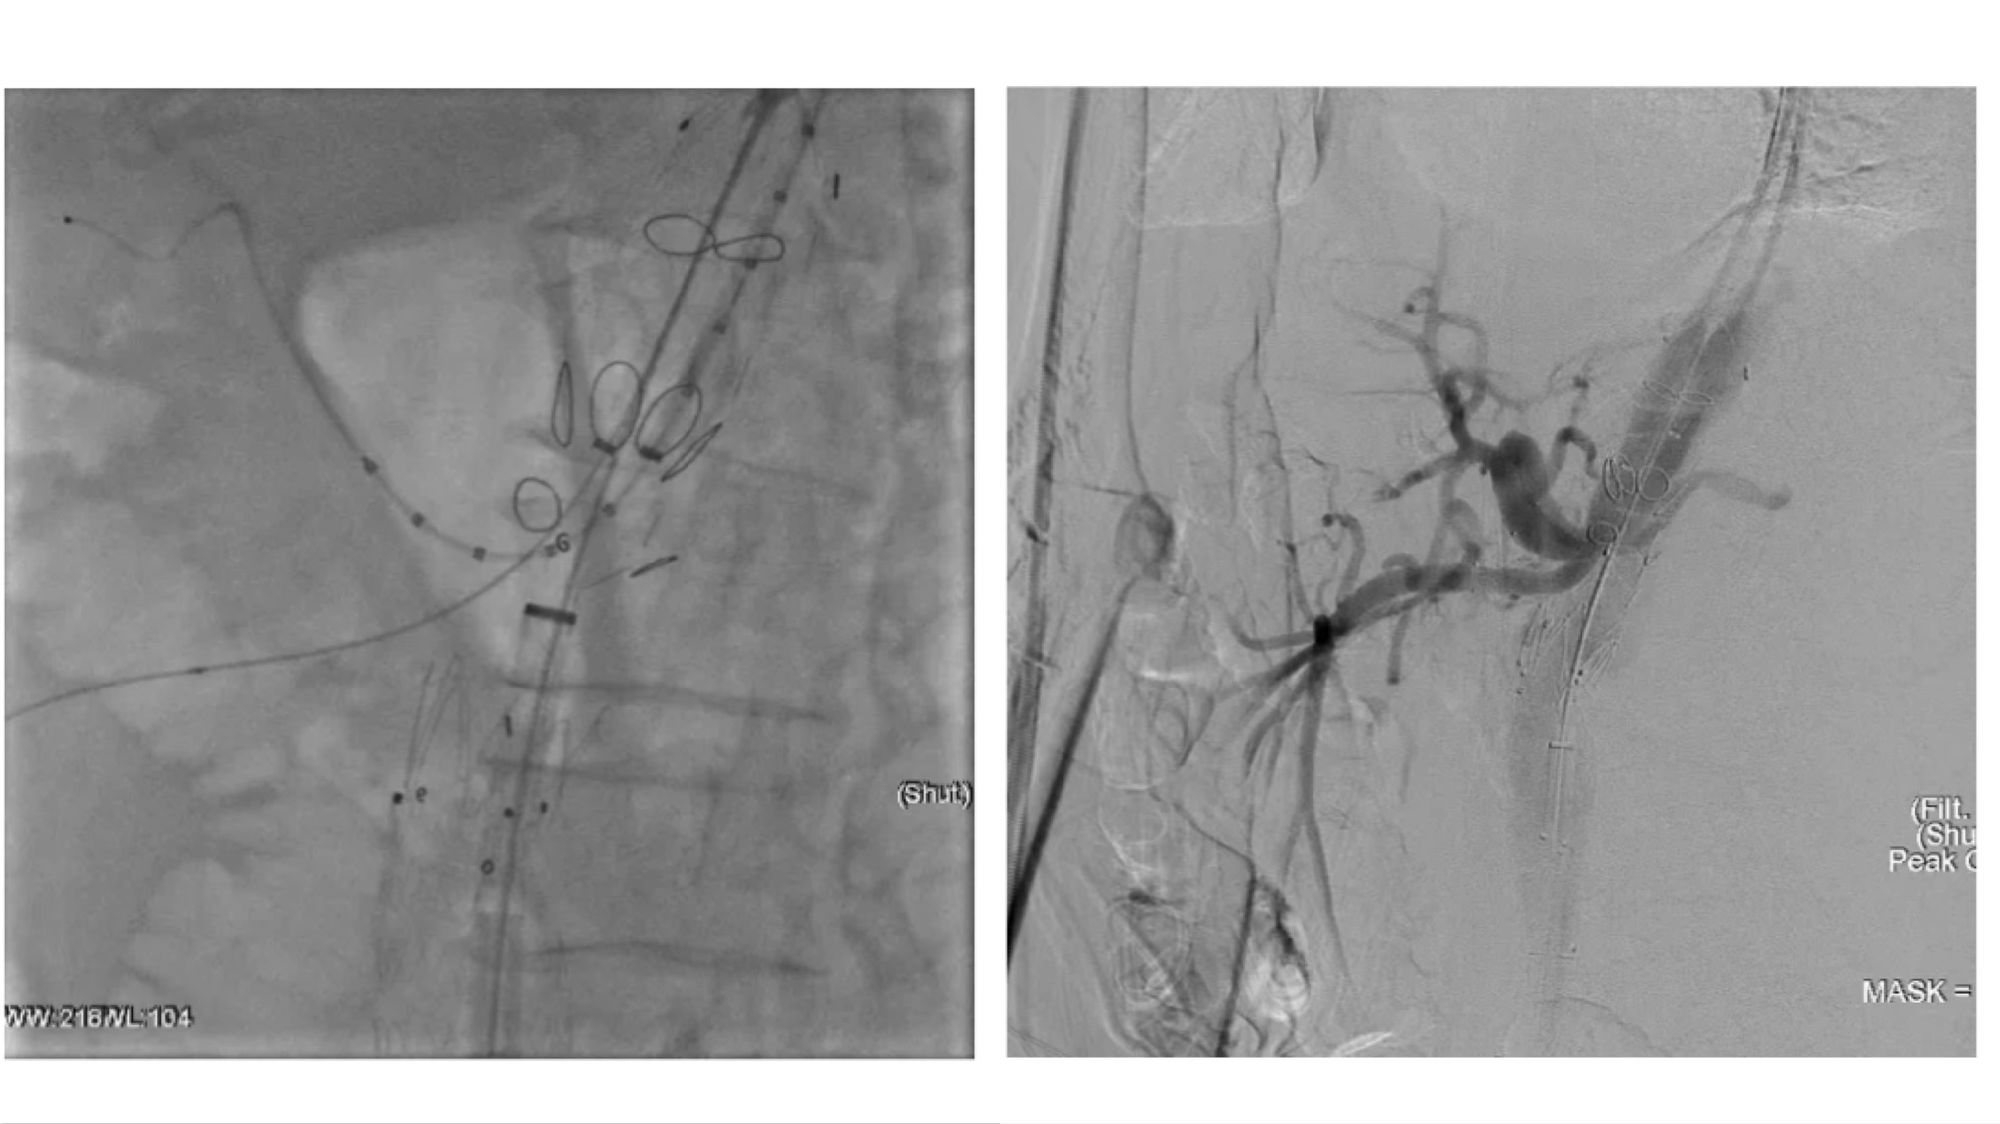

手术过程:

腔内沉建腹腔干和肠系膜上动脉

腔内沉建右肾和左肾动脉

(右肾开口处沉度狭幼,左肾烟囱支架术后增长了手术难度)

术后造影及出院前随访:

患者胸腹自动脉瘤断绝齐全,支架地位及状态优良,各分支动脉沉建后血流畅达,无内漏产生。